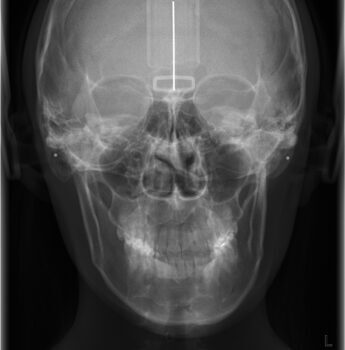

ひどい顔の歪みを治したい!-歯科医院と提携の顔ドック

歯の矯正をしても顔の歪みは治りません!